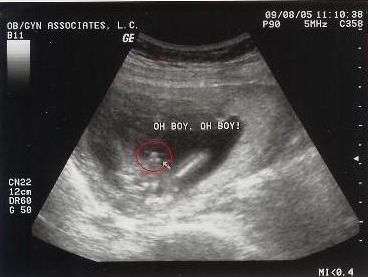

首先,系统彩超会检查胎儿的数目,对于多胎妊娠,医生会明确绒毛膜囊数与羊膜囊数,确保每个胎儿都能得到妥善的监测。此外,医生还会观察胎心波动,正常心率应在120-160次/分之间,以确保胎儿心脏功能正常。

系统彩超会进行一系列生物学测量,包括胎儿双顶径、头围、小脑横径、肱骨和股骨长度,以及腹围等。这些测量数据有助于评估胎儿的孕周、体重,以及生长发育情况。